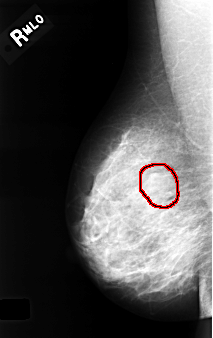

C_0334_1.RIGHT_MLO

FILE: C_0334_1.RIGHT_MLO.OVERLAY

TOTAL_ABNORMALITIES 1

ABNORMALITY 1

LESION_TYPE MASS SHAPE LOBULATED MARGINS OBSCURED

ASSESSMENT 4

SUBTLETY 3

PATHOLOGY BENIGN

TOTAL_OUTLINES 1

BOUNDARY